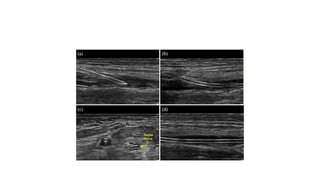

RADIAL ARTERY CANNULATION

• The radial artery is the most common

RADIAL ARTERY CANNULATION •The radial artery is the most common site for arterial cannulation.